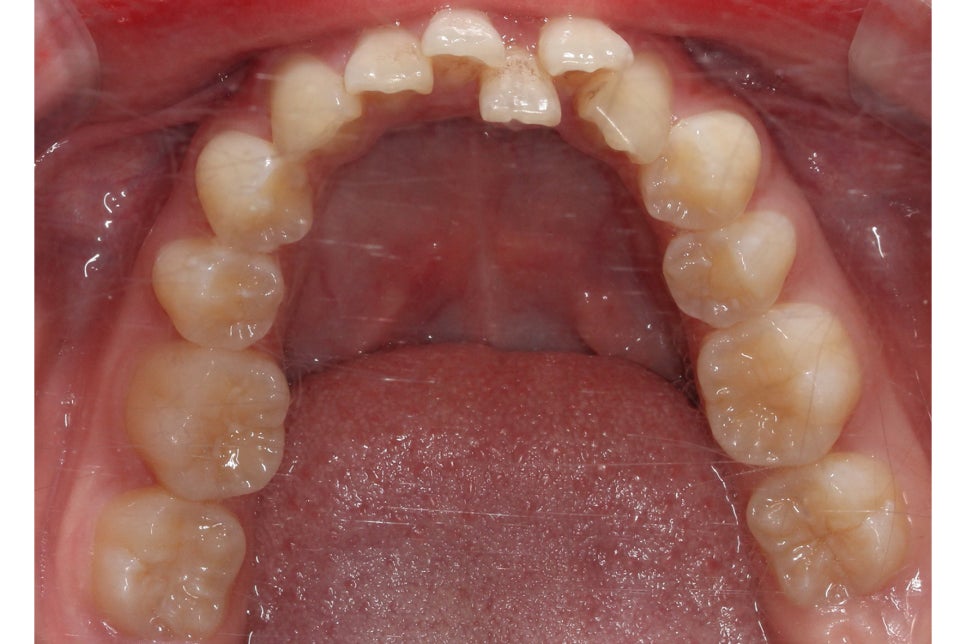

아랫니의 경우 전치부의 총생이 심하고

삐뚤어진 부분에 치석과 치태가

쌓일 위험이 있기 때문에

바른 치아 배열을 중점적으로

비발치 클리피씨교정을 진행하였습니다.

투디치과 환자분의 교정 후 아랫니의 모습을 보면

총생이 심했던 전치부 치열이 몰라볼 정도로

가지런해진 것을 확인할 수 있는데요,

삐뚤거리던 치아가 바르게 배열되면서

치석과 치태가 사라진 모습입니다.

전체적인 안모의 형태도 이상적인

곡선을 그리는 모습으로 비발치로 진행하였지만

비교적 단기간에 교정을 마무리할 수 있었는데요,